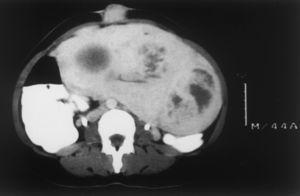

Una mujer de 44 años de edad, sin antecedentes personales ni familiares de interés, nulípara, con una fórmula menstrual de 3-4/28-30, ingresó en el servicio de ginecología por sensación de compresión abdominal. En la exploración física se apreciaba una pelvis ocupada por una masa irregular de gran tamaño (fig. 1). El servicio de dermatología fue requerido para valorar una lesión tumoral en región umbilical, de 5 años de evolución, asintomática y sin sintomatología asociada al ciclo menstrual.

Fig. 1.--TC que muestra una pelvis ocupada por una masa de gran tamaño.